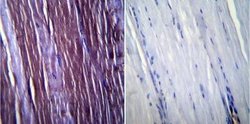

ABIN258384 IHC

Full details

Other validation